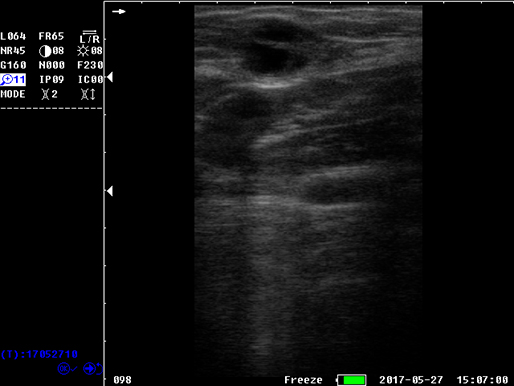

B模式 猪孕检

猪孕检

猪孕检

猪孕检